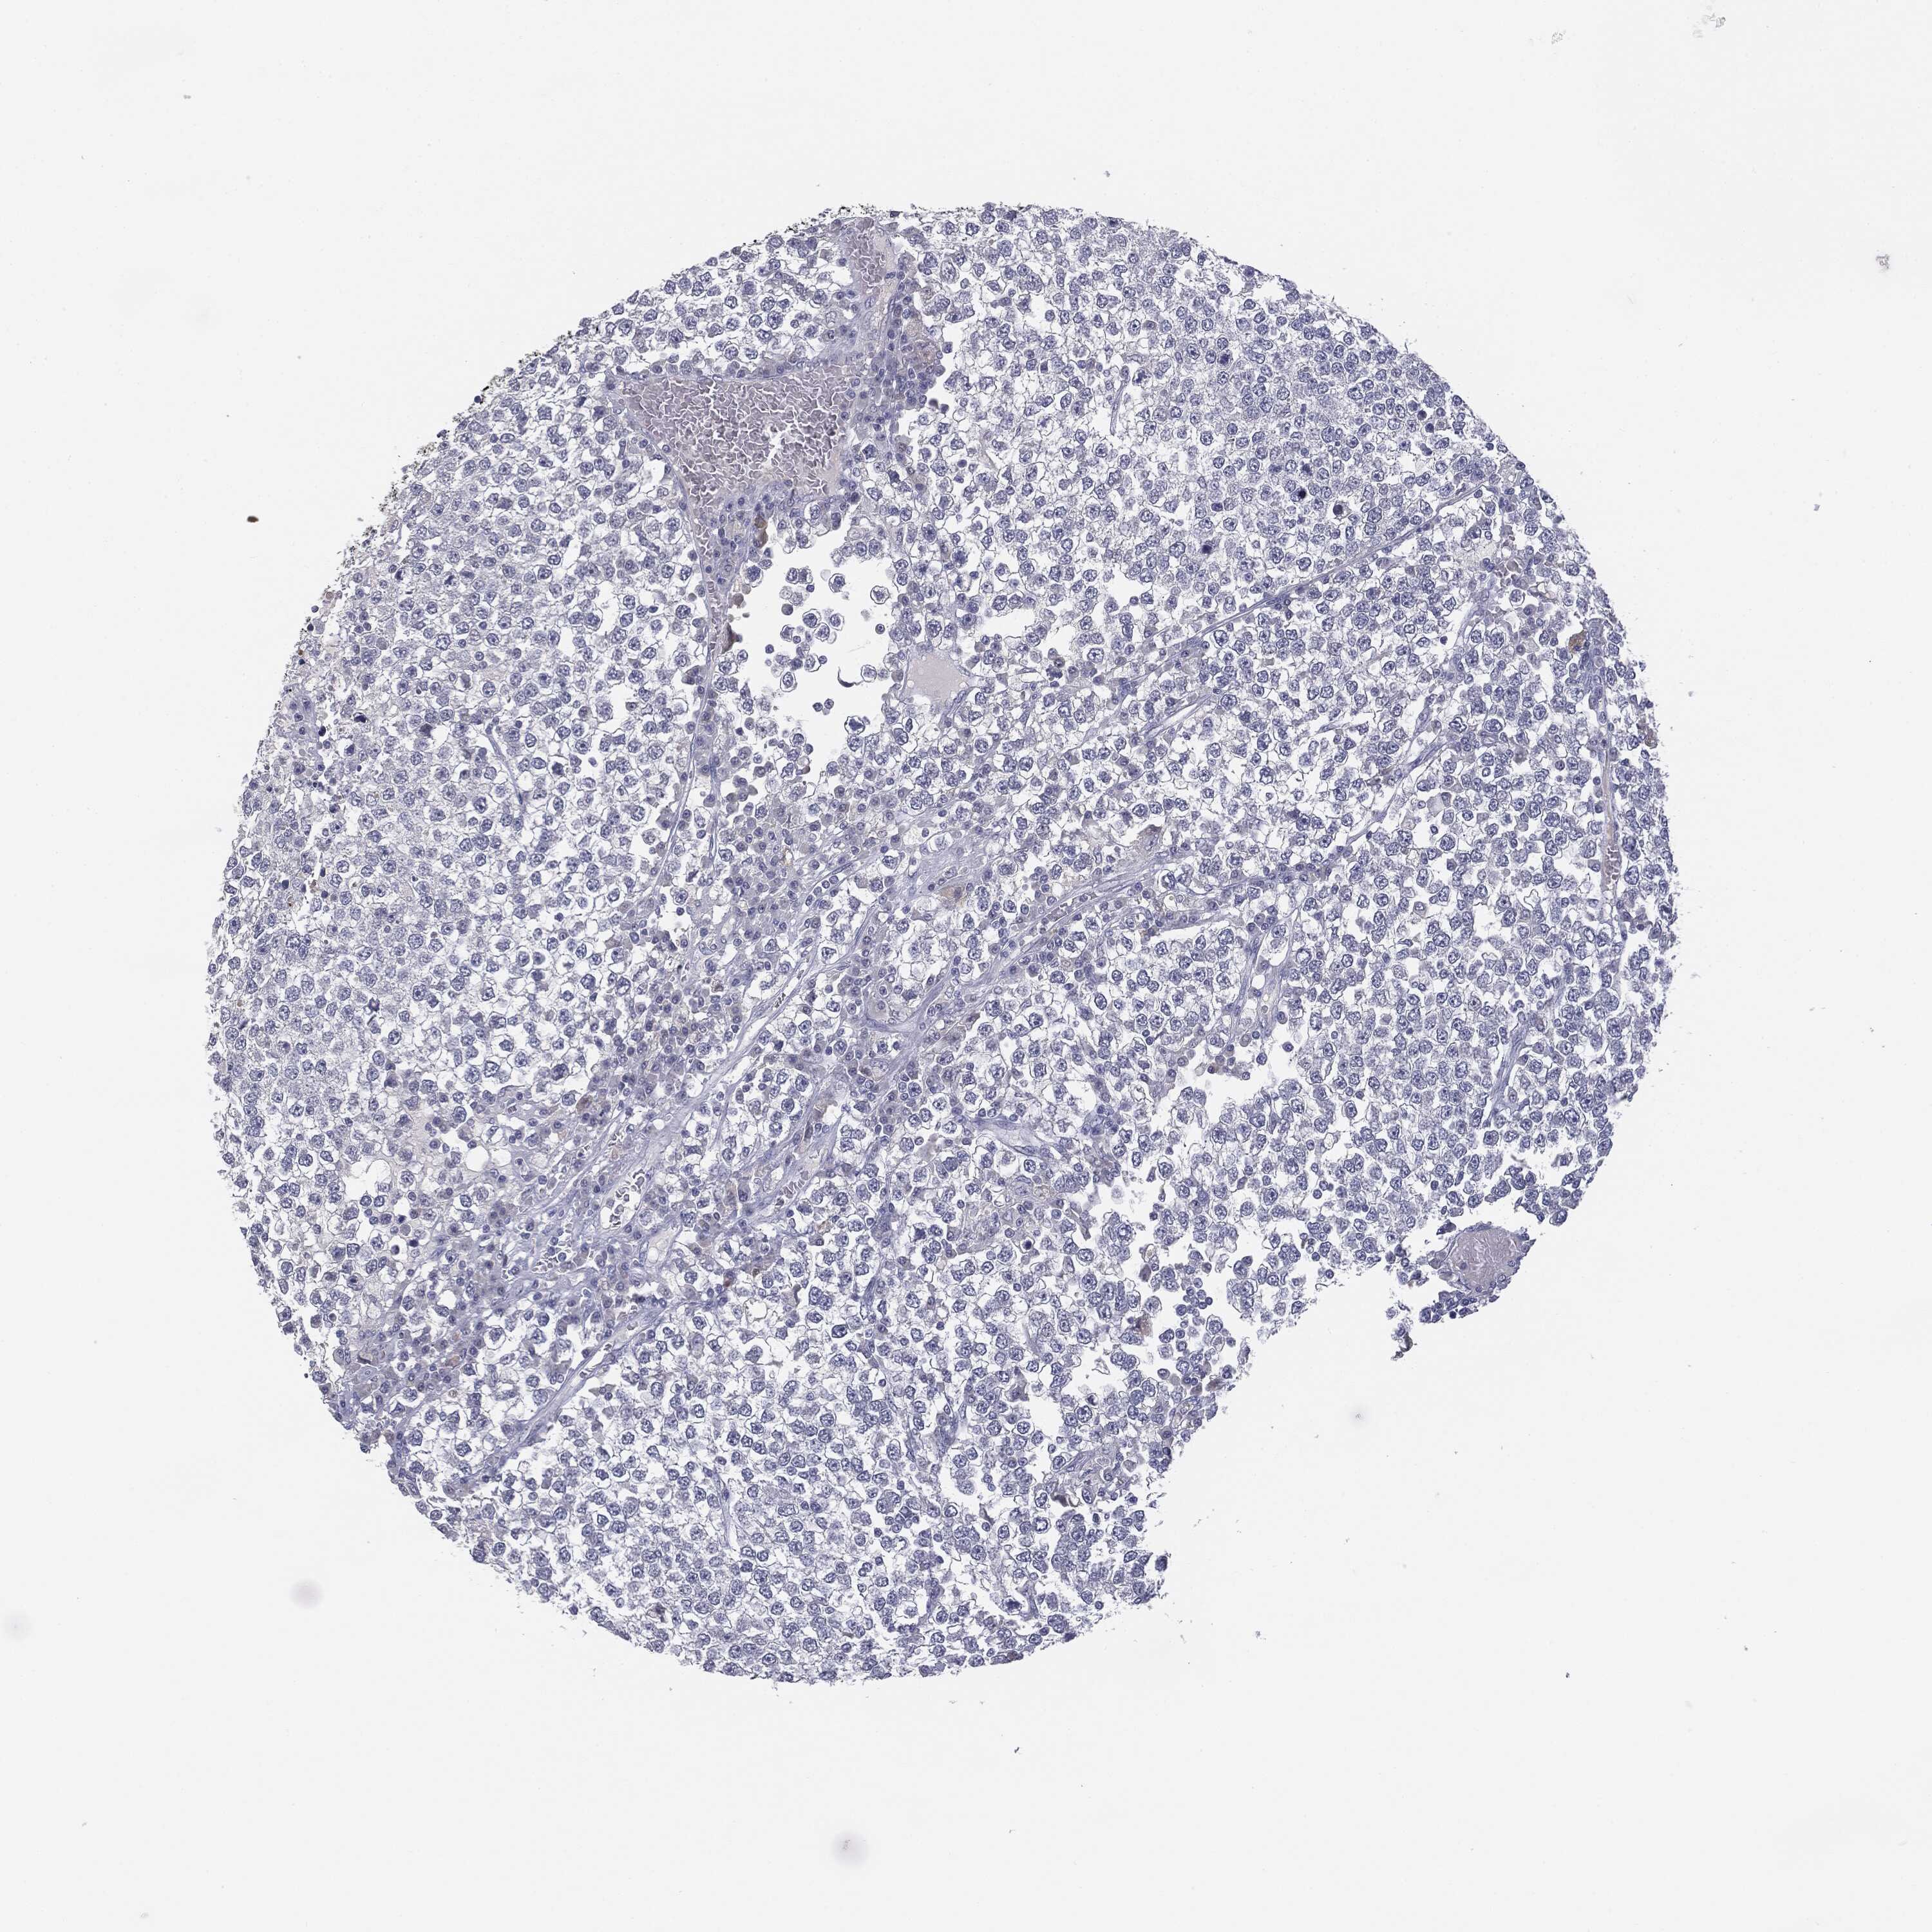

TESTIS CANCER - Protein expressioni

A mouse-over function shows sample information and annotation data. Click on an image to view it in a full screen mode. Samples can be filtered based on level of antibody staining by selecting one or several of the following categories: high, medium, low and not detected. The assay and annotation is described here.

Note that samples used for immunohistochemistry by the Human Protein Atlas do not correspond to samples in the TCGA dataset.

Antibody stainingi

Antibody staining in the annotated cell types in the current human tissue is reported as not detected, low, medium, or high, based on conventional immunohistochemistry profiling in selected tissues. This score is based on the combination of the staining intensity and fraction of stained cells.

Each image is clickable and will lead to virtual microscopy that enables deeper exploration of all samples and also displays staining intensity scores, fraction scores and subcellular localization as well as patient and tissue information for each sample.

HPA004179

HPA007235

HPA008855

CAB000036

CAB001986

CAB080102

CAB080103

Carcinoma, Embryonal, NOS

Seminoma, NOS

Teratoma, malignant, NOS

Urothelial carcinoma, High grade